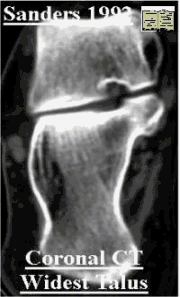

CT classification Sanders

Sanders CT Classification

Sanders - coronal CT scan - 4 types

I, nondisplaced irrespective of number of fracture lines

II, two part (split), three subtypes, IIA, IIB, and IIC, based on the location of the primary fracture line

III, three part or split depression of central fragment, subtypes included IIIAB, IIIAC, and IIIBC

IV, comminuted 4 or more fragments

The section showing the widest undersurface of the posterior facet is arbitrarily used. The talus isdivided into three equal columns by two lines.A third line is drawn just medial to the medial edge of the posterior facet. Dividing the posterior facet into three potential pieces: a medial, central, lateral and a sustentacular fragment.